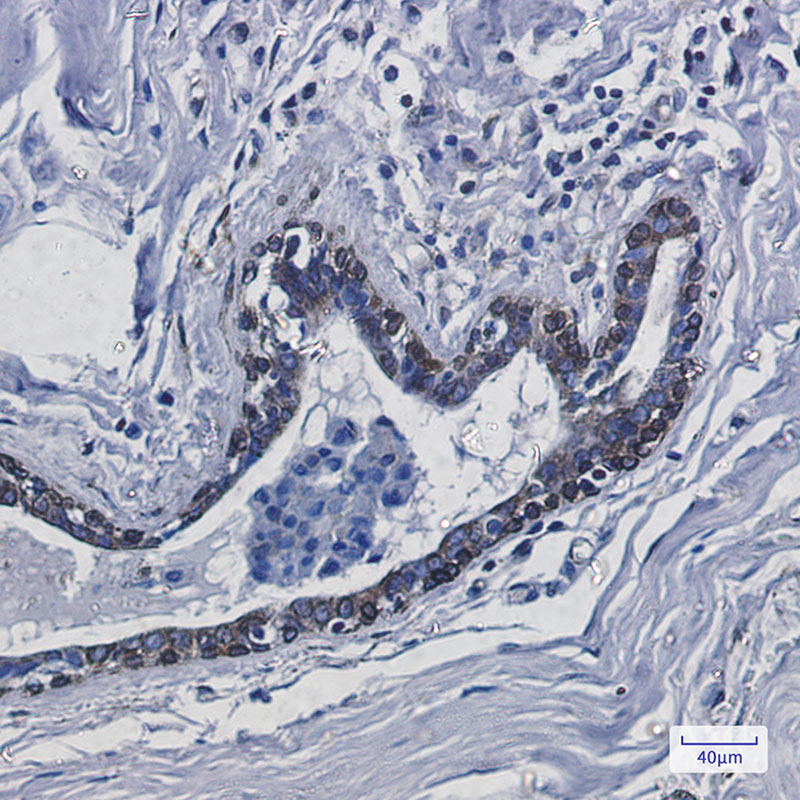

IHC 1/50-1/100 Human,Mouse,Rat

Transmembrane Protein 43 (TMEM43), also known as ARVC5 or LUMA, is a ubiquitously expressed protein localized primarily in the nuclear envelope and endoplasmic reticulum. It plays critical roles in maintaining nuclear membrane stability, cell signaling, and cell adhesion. TMEM43 is characterized by multiple transmembrane domains, though its exact structure-function relationships remain under investigation. Notably, mutations in the TMEM43 gene, particularly the p.S358L variant, are strongly linked to arrhythmogenic right ventricular cardiomyopathy type 5 (ARVC5), a hereditary disorder affecting cardiac muscle integrity and electrical conduction.

Antibodies targeting TMEM43 are essential tools for studying its expression, localization, and interactions in both normal and pathological contexts. These antibodies are widely used in techniques like Western blotting, immunofluorescence, and immunohistochemistry to assess TMEM43 levels in tissues or cultured cells. Research applications include investigating its role in cardiac pathophysiology, nuclear envelope dynamics, and potential involvement in apoptosis or mechanical stress responses. Commercially available TMEM43 antibodies are typically raised against specific epitopes, such as cytoplasmic domains, and require validation for species reactivity (e.g., human, mouse) and assay compatibility. Their utility extends to diagnostic research for ARVC5 and mechanistic studies of TMEM43's interaction with partners like emerin and lamin A/C.